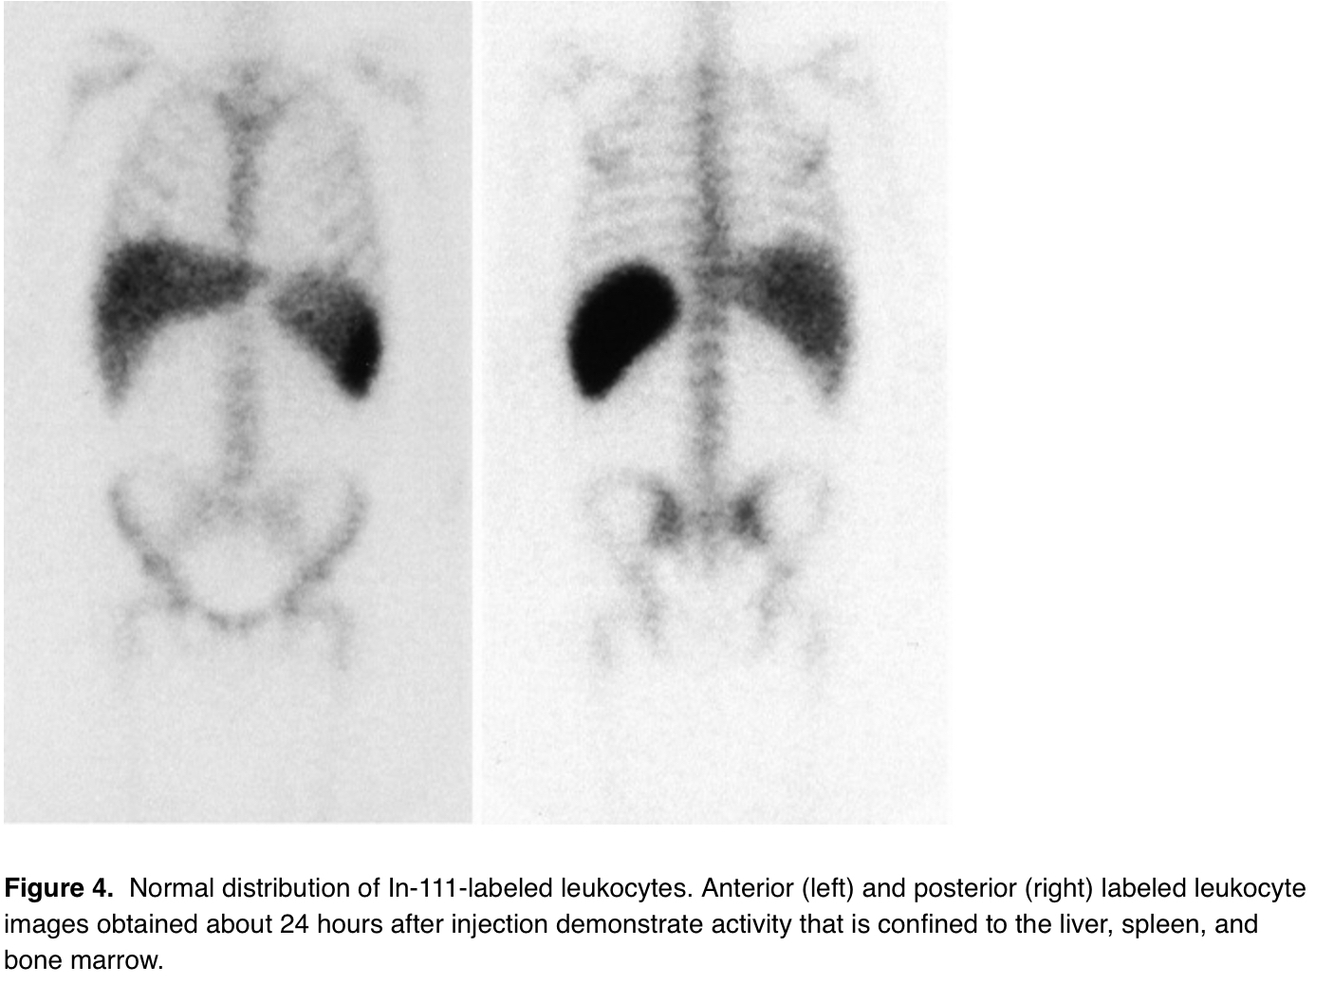

Tag for WBCs

In-111

Image difference between Tc-WBCs and In-WBCs

Indium shows no renal or GI